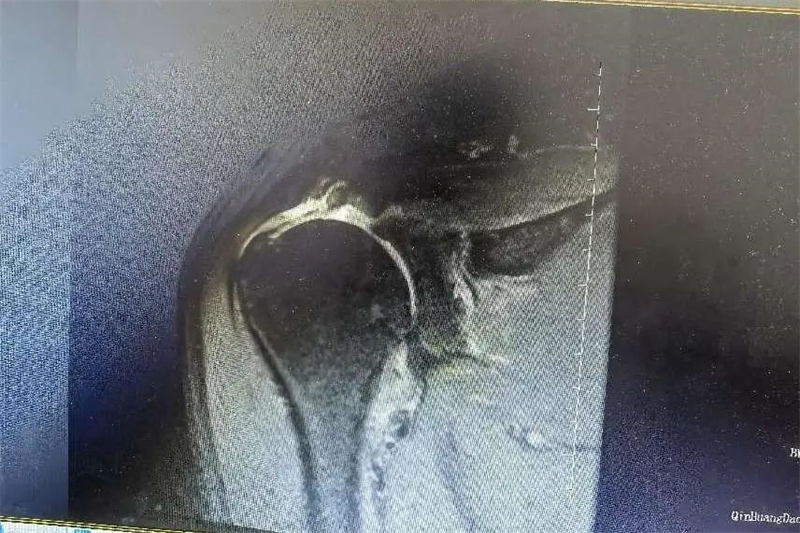

10月15日,秦皇岛41岁的张姓患者因骑车时摔伤导致右肩活动受限十余天,通过多方了解来到军工医院运动医学科就诊。运动医学科薛朝亚主任和孙超主治医师详细询问患者情况及症状。患者由于受伤以来不敢活动,继发肩关节粘连,肩关节活动度差,关节间隙不好,肩袖撕裂回缩严重,已经从正常的肱骨大结节回缩至肩胛盂上,合并肱二头肌腱脱位、肩胛下肌完全撕裂,回缩粘连,属于复杂型巨大肩袖撕裂。

肩袖是包绕在肱骨头周围的一组肌腱复合体,包括冈上肌腱、冈下肌腱、肩胛下肌腱和小圆肌腱,这些肌腱将肱骨头稳定于肩胛盂上,对维持肩关节的稳定和肩关节活动起着极其重要的作用。其中冈上肌主要负责上抬肩关节、和下压肱骨头的作用,撕裂后主要表现为疼痛和抬肩无力,肩胛下肌主要负责肩关节内旋,损伤后主要表现为内旋无力与疼痛,患者因肩袖损伤后继发关节粘连,需手术治疗。运动医学科医疗团队经术前讨论后制定手术方案,孙超医生与患者及家属详细沟通,确定手术治疗。 术前准备完毕,手术开始。医生将患者肩关节囊、肌腱松解后分别行肩胛下肌修复、肱二头肌腱固定术与冈上肌修复术。在兄弟科室的配合下,手术取得圆满成功。